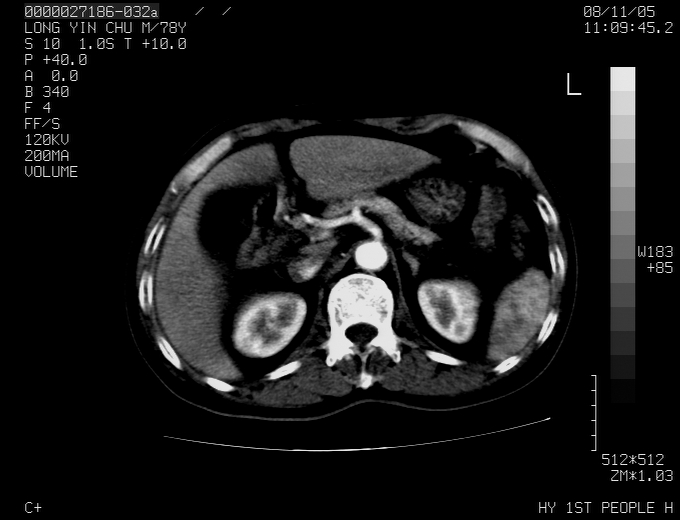

标题: CT16532:M78Y,肝脏病变,请会诊 [打印本页]

标题: CT16532:M78Y,肝脏病变,请会诊

腹胀,腹痛就诊,男性,78岁,外院b超未见异常。

考虑弥漫性肝癌并脾及双肾转移.双侧胸水.

肝脾肾转移瘤可能性大,左肾不除外梗塞,双侧胸水

考虑肝癌并双肾及脾脏转移;双侧胸腔积液。